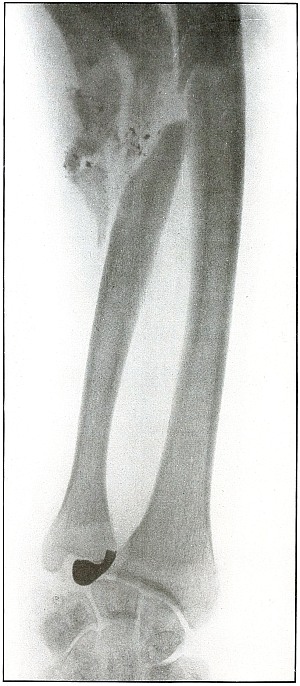

| 100. |

Gunshot fracture, elbow |

210 |

| 101. |

Gunshot fracture, radius and ulna |

212 |

| 102. |

Gunshot fracture, radius |

214 |

| 103. |

Gunshot fracture, radius |

216 |

| 104. |

Gunshot fracture, ulna |

218 |

| 105. |

Gunshot fracture, metacarpus |

220 |